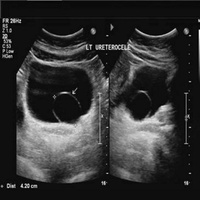

Мочевые органы и половые железы закладываются независимо друг от друга, но при дальнейшем развитии они формируют анатомически единую систему органов.Аномалии развития мочеполовых органов составляют более 30 % всех врожденных пороков развития.

Все аномалии развития почек создают условия для нарушения уродинамики, стаза мочи, инфицирования и развития тяжелых осложнений. Наиболее тяжелым осложнением у детей является пиелонефрит, при поздней диагностике которого развиваются деструктивные изменения в почке. Именно поэтому актуальными становятся ранняя диагностика и своевременная коррекция пороков развития органов мочеполовой системы.